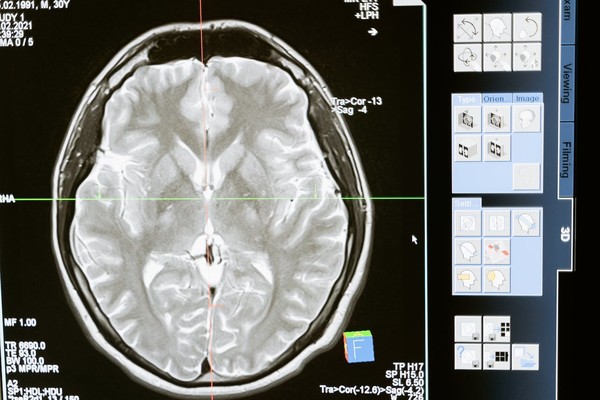

[메디컬리포트뉴스 유제원 기자] 뇌종양은 두개골뿐만 아니라 뇌 주변의 뇌신경, 뇌막, 뇌혈관, 두피 등에서 발생할 수 있다. 보건의료빅데이터에 따르면, 뇌종양 환자는 매년 꾸준히 증가하는 추세다. 양성 뇌종양 환자는 2020년 4만 7675명에서 2022년 5만 5382명으로 증가했으며, 악성 뇌종양 환자는 같은 기간 동안 1만 1603명에서 1만 2140명으로 늘어났다. 악성 뇌종양 중 하나인 교모세포종은 매년 약 1,000명이 발생하는 것으로 알려져 있다.

뇌종양은 크게 양성과 악성으로 나뉜다. 양성 뇌종양은 주로 뇌 바깥에서 발생하는데 성장 속도가 느리다. 이 중 뇌수막종이 가장 많고 뇌하수체 종양이나 청신경초종도 흔히 발생한다.

반면, 악성 뇌종양은 빠르게 성장할 뿐 아니라 주위 조직으로 침투해 정상 뇌조직을 파괴하기 때문에 치료가 어려운 경우가 많다. 특히 전이성 뇌종양은 다른 장기의 암이 뇌로 전이되어 발생하는 경우가 상당하다.